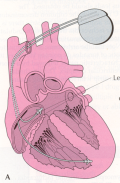

Defibrillators (ICDs) are useful in people who seem to be at risk from a life threatening arrhythmia. The device works as a pacemaker if required but can also deliver a shock to the heart if the rhythm should degenerate, restoring normal rhythm.